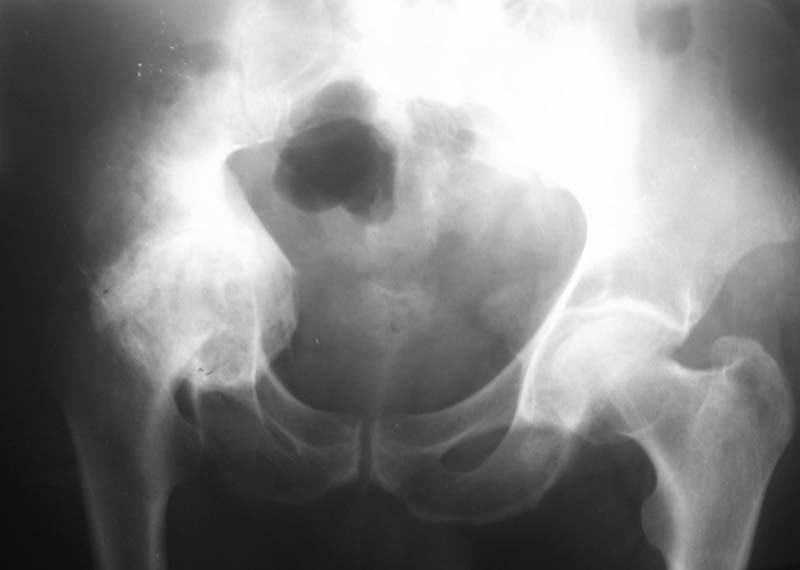

Мужчина, 54 г. В 12 лет перенес травму правого тазоберенного сустава.

Клинически движений в суставе нет, хотя при ходьбе беспокоят боли.

Предполагаем имплантацию <чашки> протеза в сформированное ложе без удаления головки бедра.

Ваше решение абсолютно адекватное и возражений нет, но проблема будет не в этом. У Вас будут сложности в 1) правильной ориентации чашки относительно истинной вертлужной впадины и 2) создании необходимого

"оффсета", попросту говоря, будет крайне сложно "оторвать" бедро от таза. Для этого мы в своей практике пользуемся расширенным передним и задним релизом, как правило, на это уходит достаточно много времени.